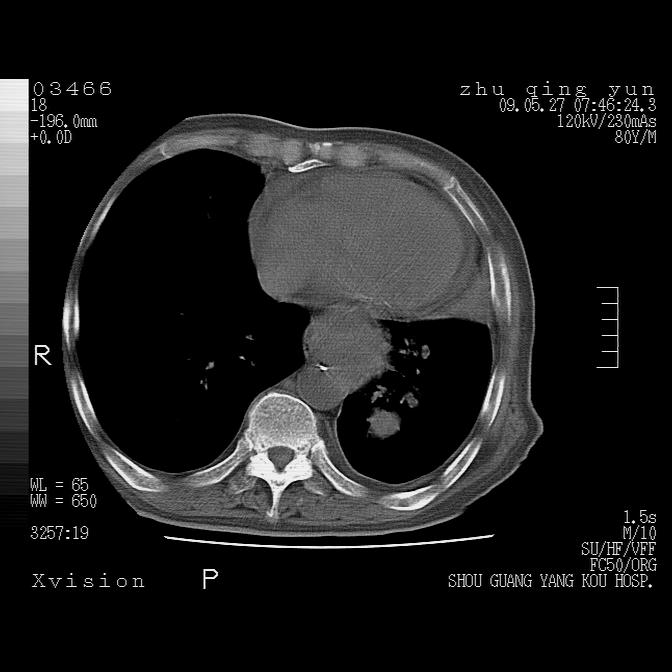

1)考虑左肺中央型肺癌并阻塞性肺炎,后下纵隔受侵伴纵隔淋巴结转移。2)双侧少量胸腔积液,胸膜增厚。3)心包积液。

双侧胸腔积液。

左侧中心型肺癌并纵隔淋巴结广泛转移.心包积液

1)考虑左肺中央型肺癌并左肺下叶阻塞性肺炎、不张;左胸膜腔积液、心包积液、纵隔淋巴结转移;癌肿累及左心房。2)左心室大。冠状动脉壁钙化斑。

考虑左肺中央型肺癌并左肺下叶阻塞性肺炎、不张;左胸膜腔积液、心包积液、纵隔淋巴结转移;癌肿累及左心房